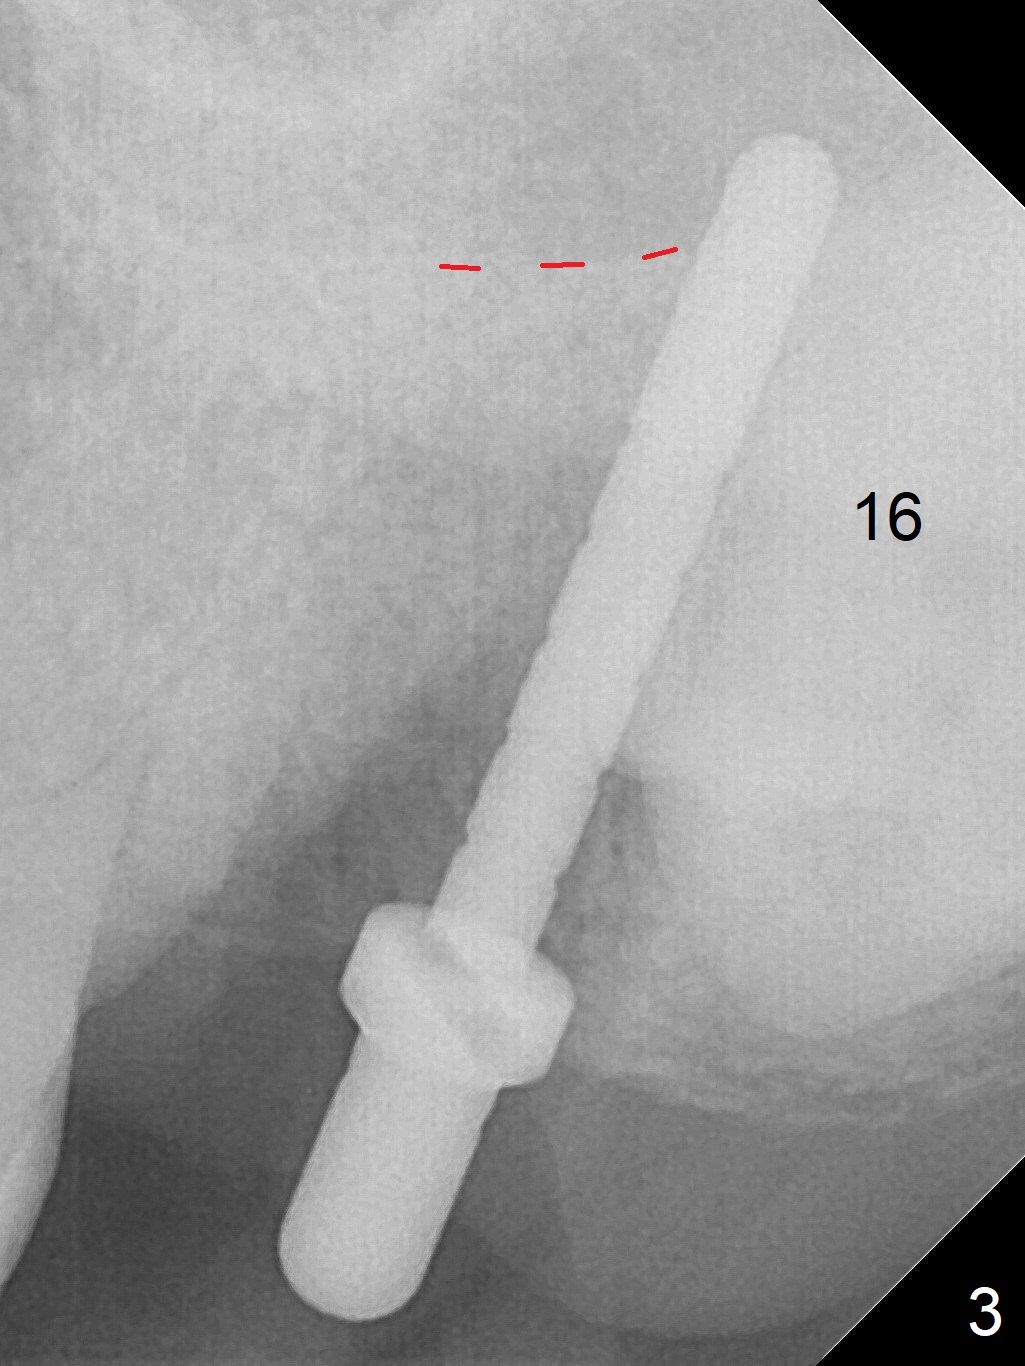

Extraction of the tooth #15 with short clinical crown (suggesting bruxism, Fig.1) reveals a vertical root fracture (Fig.2 <). It seems unnecessary and difficult to create osteotomy in the mesial slope. What can be done is to place starter and 2 mm drills as mesial as possible (Fig.3 (red dashed line: sinus floor). After use of Lindamann bur to move the osteotomy mesially and sequential osteotomy until 3.8x18 mm, a 4.5 mm tap is inserted with clearance from the impacted tooth #16 (Fig.4). A 5x15 mm implant is placed with >60 Ncm with clearance from the 3rd molar (Fig.5,6). If the impacted tooth were removed, the primary stability is expected to be reduced. Impression is taken 6 months postop with 19/20 implants (Fig.7). The bone graft remains in the crestal area immediately and 11 months post cementation (Fig.8,9 *). In the other word, new crestal bone forms after extraction.